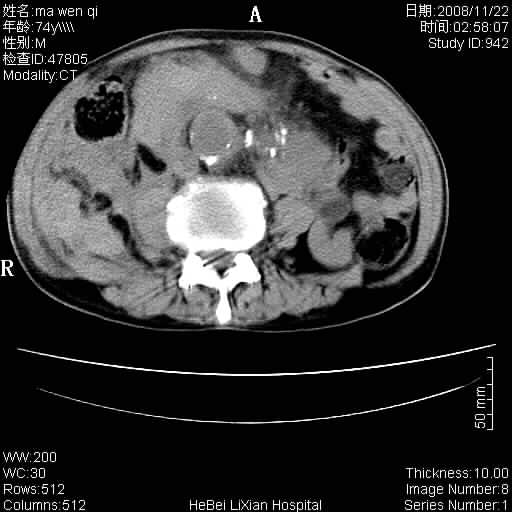

患者男 74岁.突然昏迷,休克6小时.血压70/30,头颅ct未见异常,既往体健.

补充病史,保留导尿10小时,尿袋内只有少许尿液,患者于住院后15小时后去世.

腹主动脉、双侧髂动脉夹层动脉瘤破裂出血进入腹腔。

1)考虑双侧髂动脉瘤并右侧动脉瘤破裂出血,右侧腹膜后及腹腔积血。2)双侧腹股沟疝。

1)考虑,腹主动脉、双侧髂动脉夹层动脉瘤破裂伴右侧腹膜后及腹腔积血。2)双侧腹股沟疝。